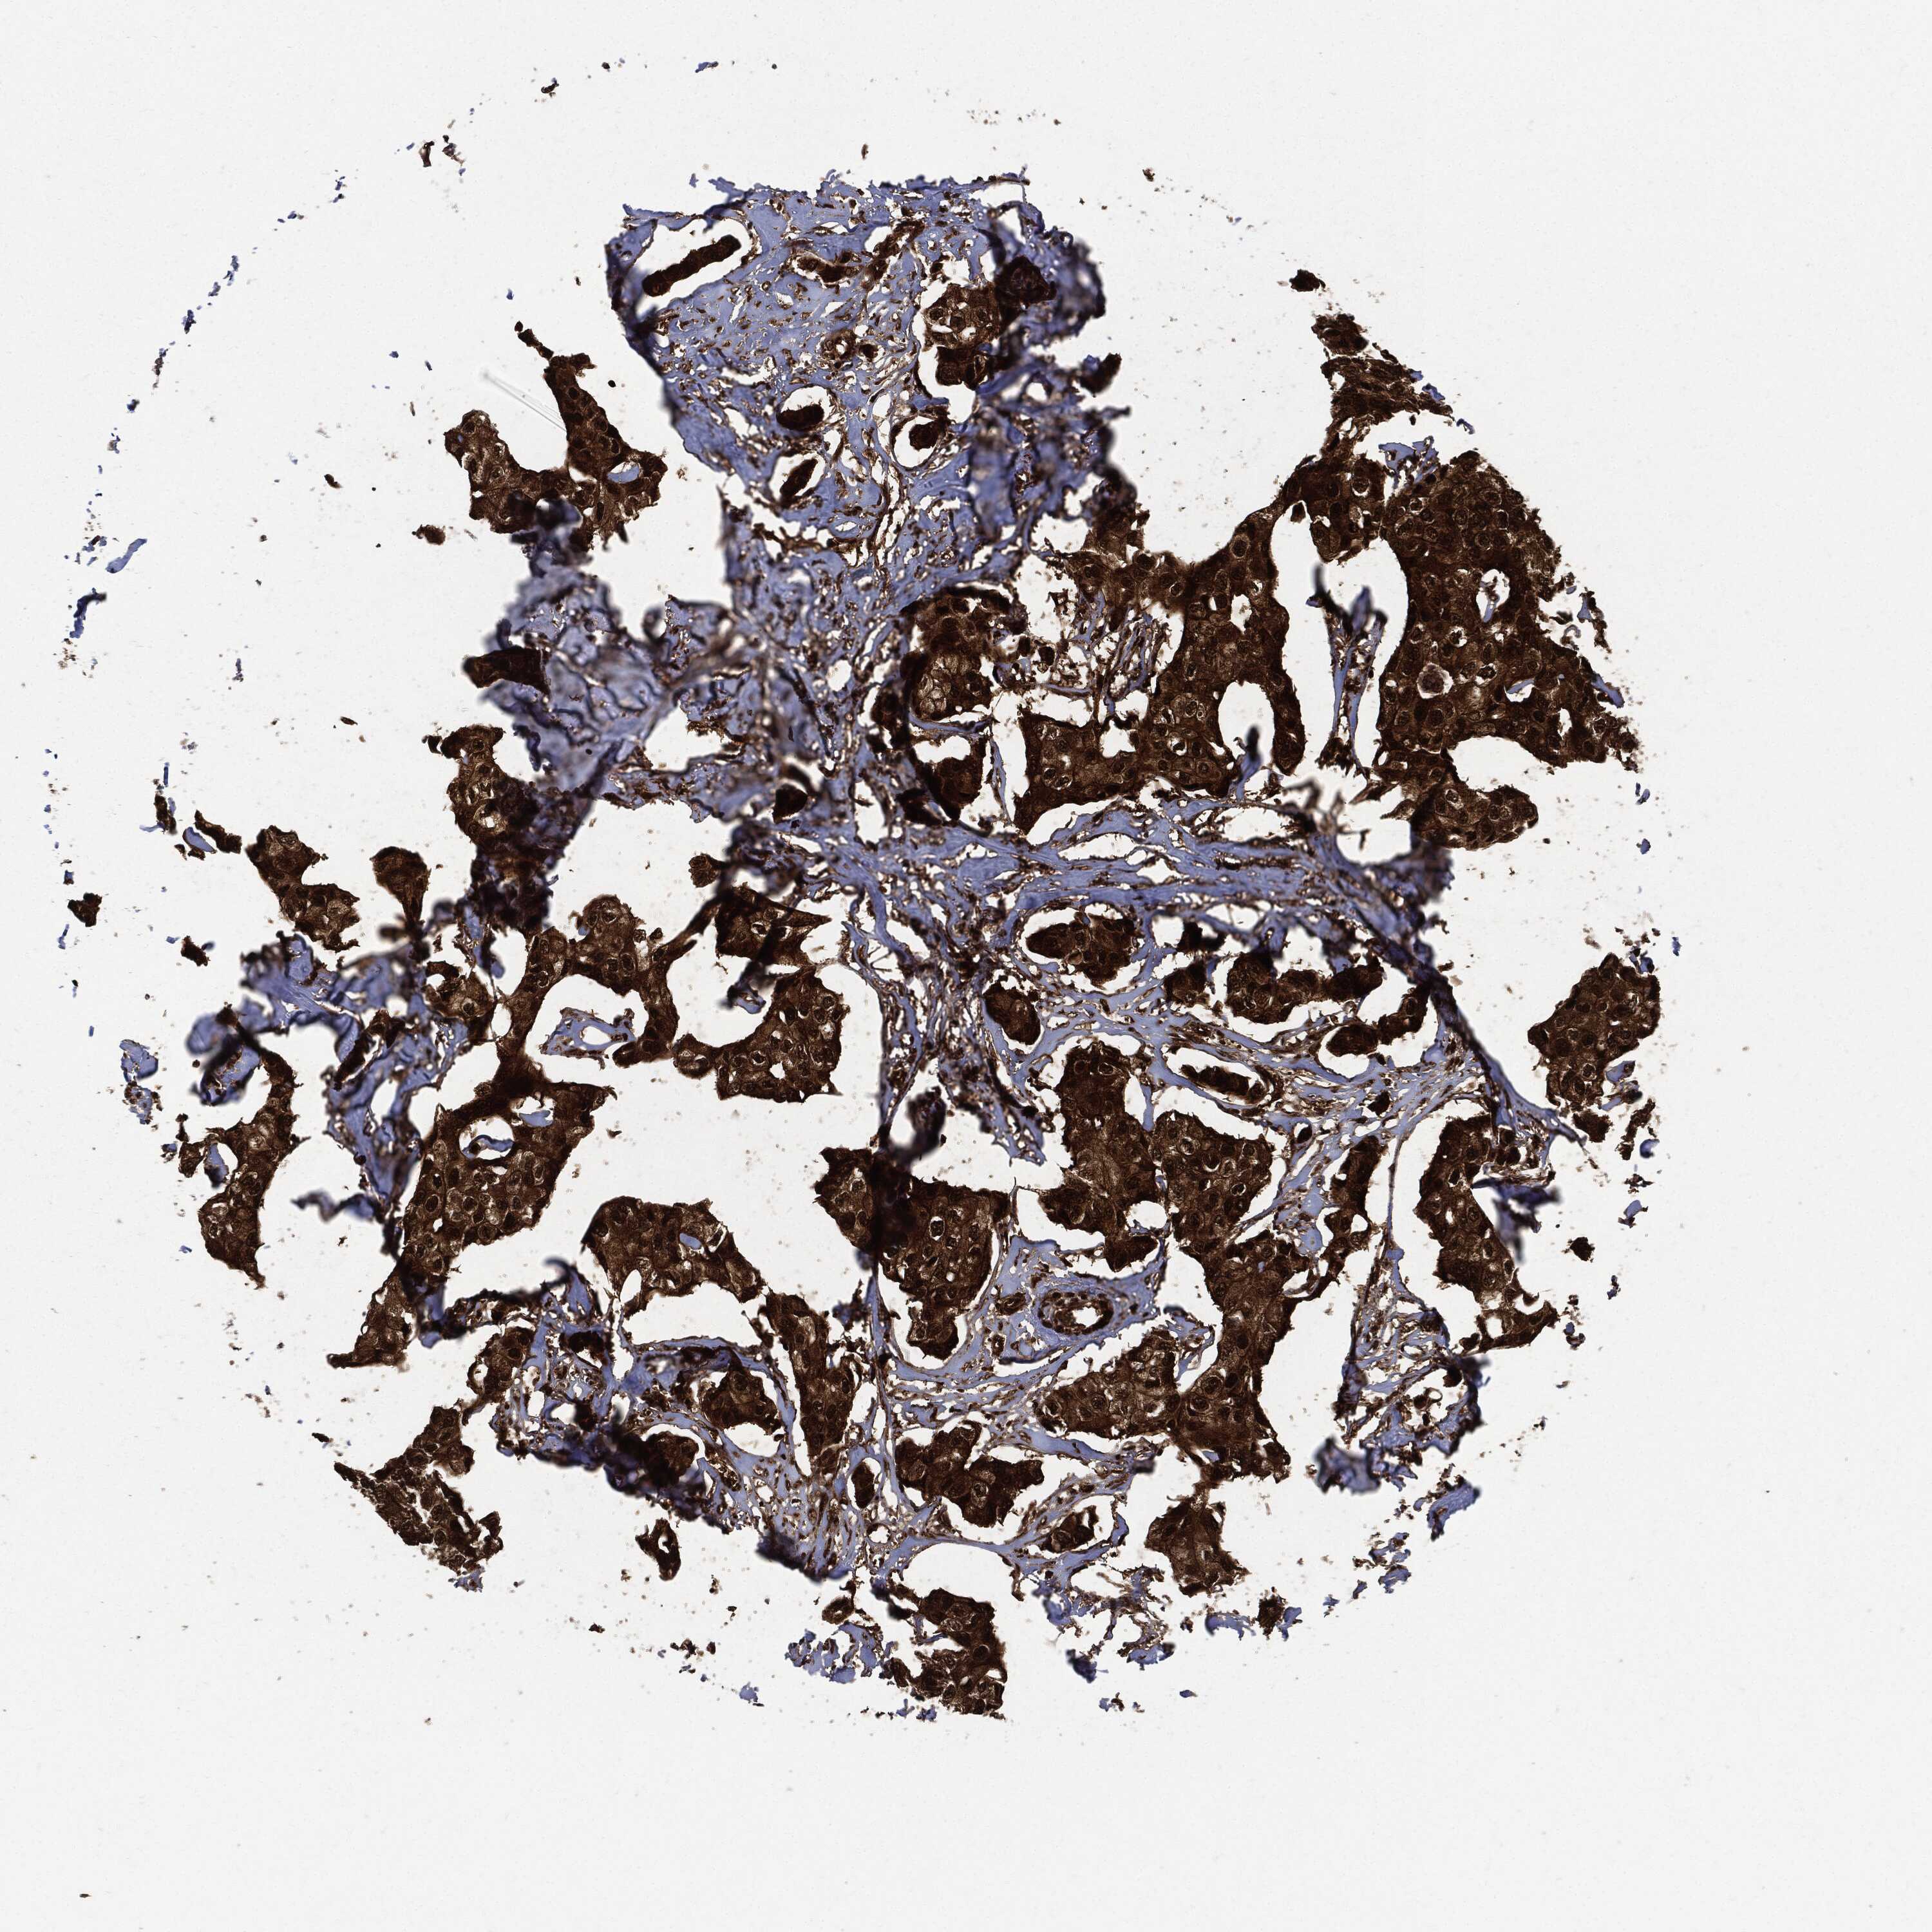

BRCA TCGA BRCA VALIDATION PROTEIN EXPRESSION

ANTIBODIES

AND

VALIDATION